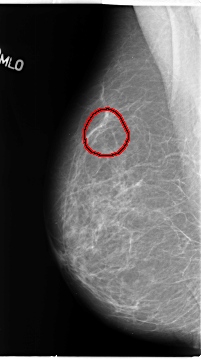

B_3121_1.RIGHT_MLO

RIGHT_MLO LINES 4664 PIXELS_PER_LINE 2608 BITS_PER_PIXEL 12 RESOLUTION 50 OVERLAY

FILE: B_3121_1.RIGHT_MLO.OVERLAY

TOTAL_ABNORMALITIES 1

ABNORMALITY 1

LESION_TYPE CALCIFICATION TYPE PLEOMORPHIC DISTRIBUTION CLUSTERED

ASSESSMENT 4

SUBTLETY 3

PATHOLOGY BENIGN

TOTAL_OUTLINES 1

BOUNDARY